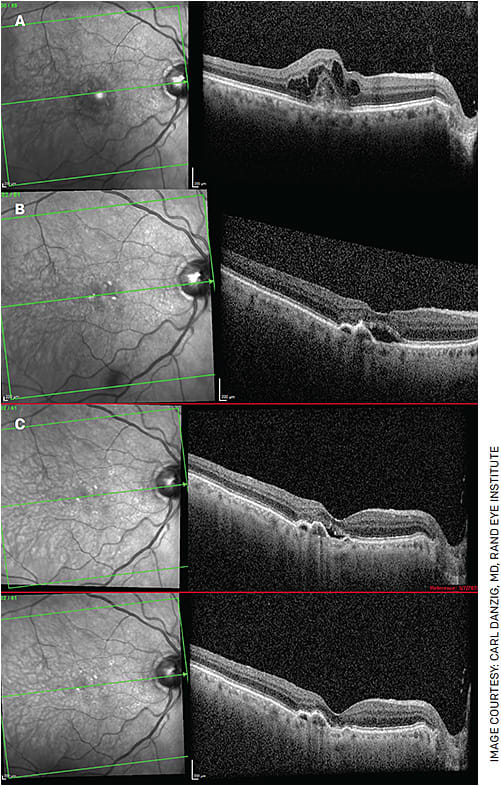

FIGURE 2. A 94-year-old gentleman has been receiving injections monthly since 2013. Figure 2A shows choroidal neovascularization with CME. This patient is highly compliant, averaging 11-12 injections per year, and was able to maintain 20/30 vision for many years. Even with a trial of Q2W injections, his subretinal fluid never resolved. Despite his frequent injections over the years, his vision declined somewhat to 20/60. Despite monthly injections, the patient had persistent subretinal fluid in February 2018 (Figure 2B). In March 2022, he received his first Vabysmo injection and, for the first time in almost 9 years, has been without subretinal fluid (Figure 2C following his first Vabysmo injection). Unfortunately, his vision remains 20/60, but he is hopeful he can extend his injection interval in the near future.